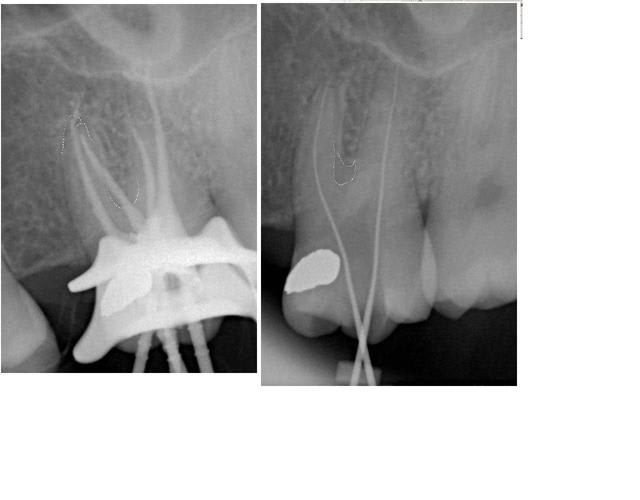

Pour ceux que le sujet amuserait encore, j'ai joué avec la loupe:

- on voit bien un dédoublement au départ de la racine mésiale à partir de la furcation, sur la radio broches en place

- on arrive à souligner la présence de deux apex mésiaux sur la radio post-opératoire

Néanmoins ce cliché est troublant dans la mesure où les trabéculations inter-radiculaires paraissent traversées par le thermafil.

L'explication me semble pouvoir être tirée de la connaissance de la morphologie la plus courante de ce type de racine à MV2, constituant le plus souvent un canal accessoire qui se traduit morphologiquement par une extension en voile de la racine principale donc très peu radio-opaque.

puisque vous insistez,regardez l'ouverture de la chambre pulpaire et l'emplacement de la lime

autopsie d'une endo;))